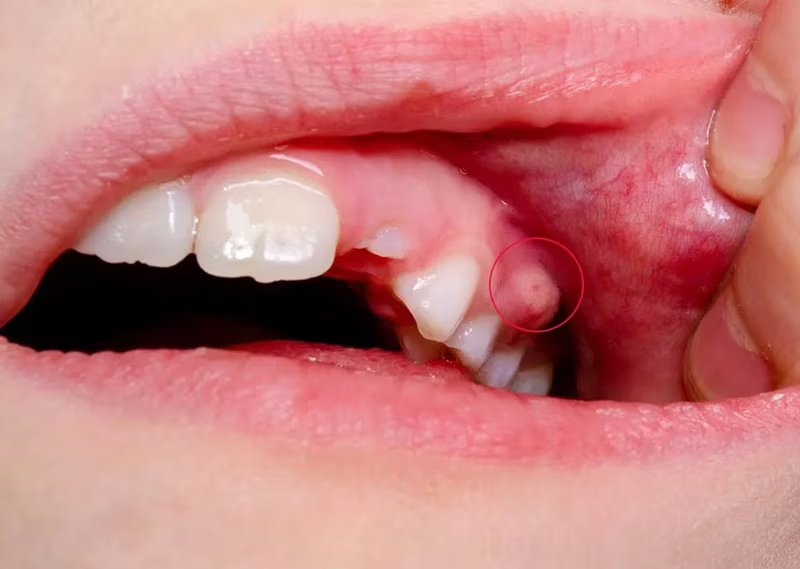

Một điểm đặc trưng của áp xe nha chu là mủ bị “kẹt” trong túi nha chu, không thoát ra ngoài. Áp lực nội mô tăng lên làm người bệnh đau dữ dội, cảm giác như răng bị đội lên hoặc cộm khi cắn. Đây là giai đoạn cấp tính cần xử trí nhanh vì mủ càng tích tụ, mô quanh răng càng bị phá hủy. Do đó, điều trị áp xe quanh răng cấp không thể trì hoãn.

Điểm quan trọng trong lâm sàng là nhận diện đúng áp xe để điều trị sớm. Áp xe quanh răng cấp thường gây đau dữ dội, sưng khu trú vùng nướu, có thể xuất hiện mủ hoặc hơi thở hôi. Răng đau khi gõ hoặc khi cắn, đôi khi có cảm giác răng “dài ra” do mô quanh răng phù nề. Đây là khác biệt so với đau răng do nhạy cảm đơn thuần.

Bước quan trọng nhất trong điều trị áp xe cấp là dẫn lưu mủ áp xe. Khi mủ được thoát ra, áp lực trong mô giảm nhanh, người bệnh sẽ thấy giảm đau rõ rệt. Dẫn lưu có thể thực hiện qua túi nha chu hoặc rạch dẫn lưu tùy mức độ sưng. Đây là bước mang tính “giải áp” và là nền tảng để các phương pháp khác phát huy hiệu quả.